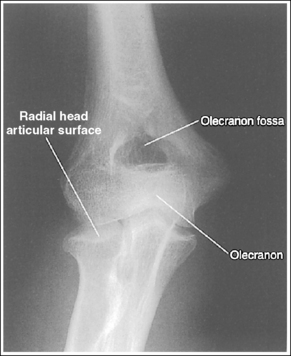

The capitulum-radius joint is either partially or completely closed, and the radial head articulating surface is demonstrated. The olecranon process is situated within the olecranon fossa, and the coronoid process is visible on end.

• The anatomical relationships of the elbow on an AP forearm projection are slightly different from those on an AP elbow projection because of the difference in centering of the central ray. The central ray is placed directly over the elbow joint for an AP elbow projection but is centered distally to the elbow joint, at the midforearm, for an AP forearm projection. With distal centering, diverged rays record the elbow joint image instead of straight central rays, much the same as if the central ray were angled toward the elbow joint. Imaging the elbow with diverged rays projects the radial head into the capitulum-radius joint and causes the anterior margin of the radial head to project beyond the posterior margin, demonstrating its articulating surface.

• Effect of elbow flexion. The positions of the olecranon process and fossa and the coronoid process are determined by the amount of elbow flexion. Accurate forearm positioning requires us to position the elbow in full extension, which places the olecranon process within the olecranon fossa and demonstrates the coronoid process on end. When a forearm image is taken with the elbow flexed and the proximal humerus elevated (Figure 4-60), the olecranon process moves away from the olecranon fossa and the coronoid process shifts proximally. How far the olecranon process is from the fossa depends on the degree of elbow flexion. The greater the elbow flexion, the farther the olecranon process is positioned away from the fossa and the more foreshortened is the distal humerus.